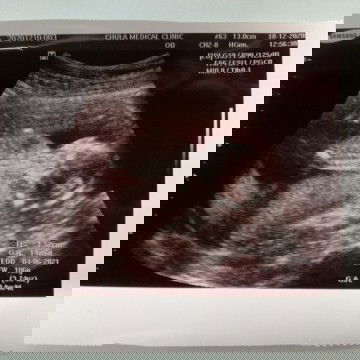

ตั้งครรภ์14วีค

14week6day น้ำหนัก106กรัม ถือว่าน้ำหนักปกติไหมคะแม่ๆ ในเห้นตอนซาวด์หมอบอกว่า ดิ้นเก่งมากและเห้นโชว์ขามาให้ด้วย แข็งแรงดีทุกอย่างคะ ดีใจมาก ที่เห้นลูกครั้งแรก น้ำตาแทบคลอ 😂😂 เพศยังไม่รู้คะน้องหนีบขาไว้ ไว้หมอนัดจะอัปเดตอีกทีนะคะ แม่ๆคนไหนซาวแล้วบ้างคะ มาอวดกันโหน่ยยย

กำหนดคลอด

แม่ๆคนไหน รู้กำหนดคลอดแล้วบ้างคะ บ้านนี้ท้องได้7วีคแล้ว กำหนดคลอด 11มิย.64